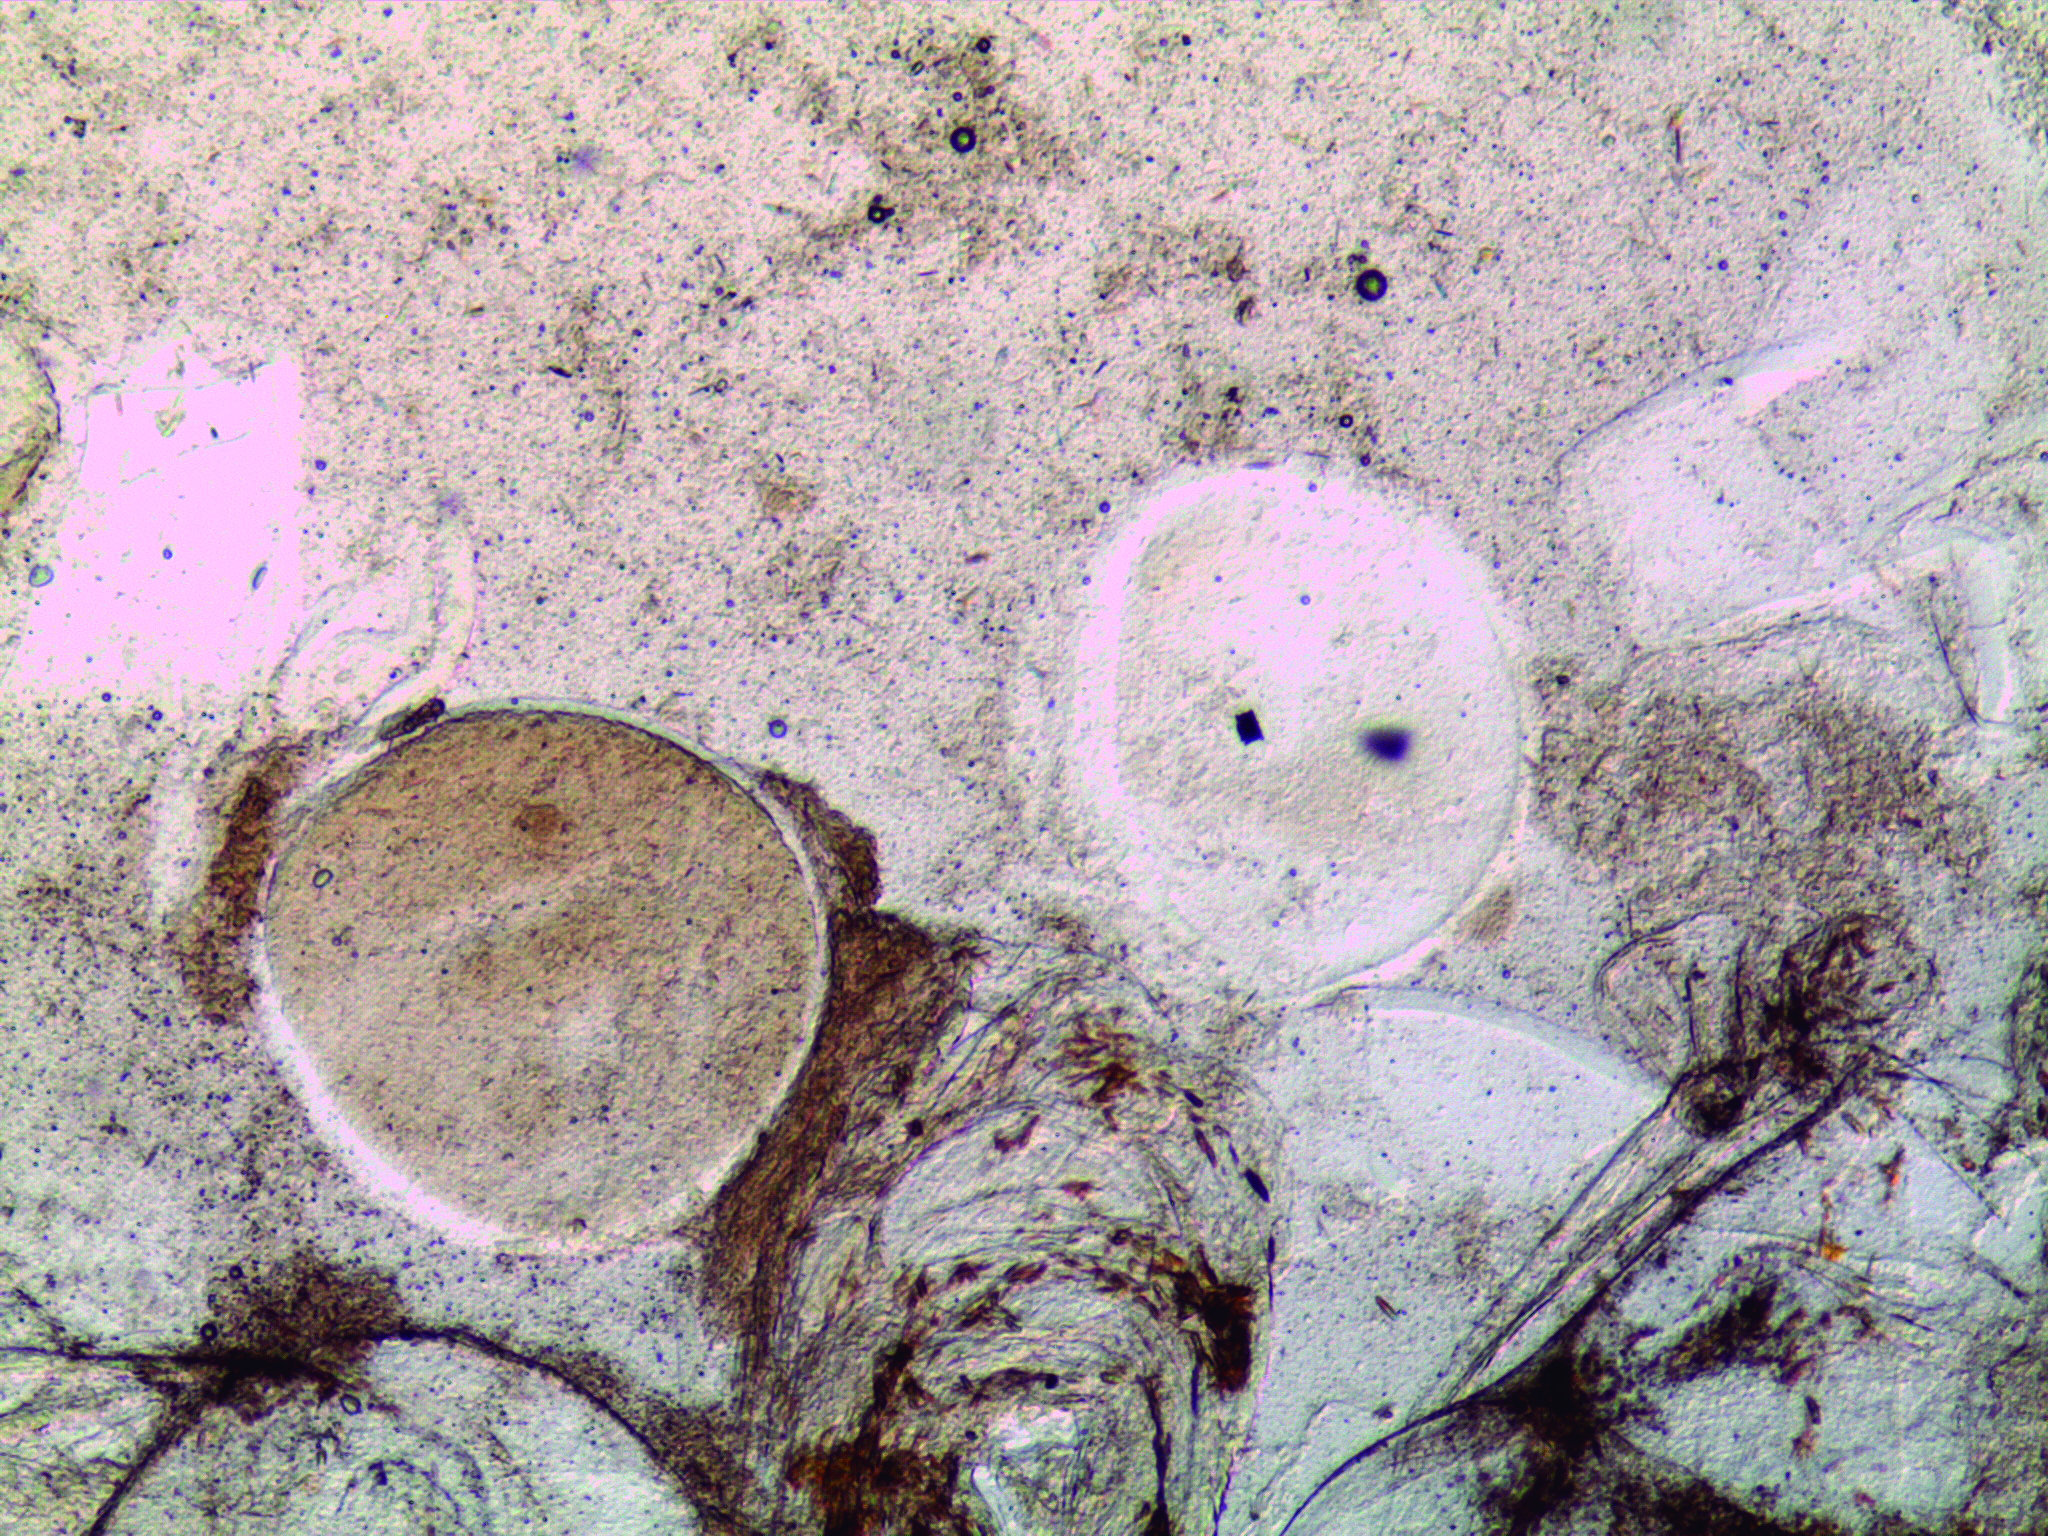

Epitheliocystis

Agent: Order Chlamydiales (Obligate intracellular bacterial pathogens). Traditionally, bacteria from the phylum Chlamydiae were the only known pathogenic agents, but etiology is now recognized as being more complex, including a range of Proteobacteria.

Symptoms: Sea bream and, less commonly, sea bass are affected. Caused by an intracellular bacterium that replicates within gill epithelial cells, leading to hypertrophy and that compromise gill function. Severe infections may cause hyperventilation and mortality.

Control: Antibiotic therapy response is variable. No vaccine is available.